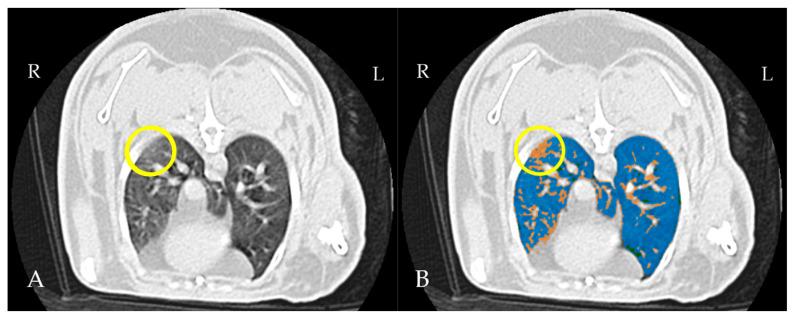

Rabbits are commonly affected by subclinical lung diseases. Computed tomography (CT) is the gold standard for diagnosing rabbit lung diseases but is not widely available and requires anesthesia, delaying diagnosis. Lung ultrasound (LUS) has emerged as a radiation-free, bedside diagnostic tool in human and veterinary medicine, though its use in rabbit medicine is not routine. This study aimed to evaluate LUS for detecting subclinical lung lesions in rabbits. Thirty healthy, five-month-old male New Zealand white rabbits underwent lung ultrasound, exploring four regions in each hemithorax, followed by thoracic CT under sedation with midazolam and butorphanol. The ultrasound images were scored as positive or negative, and the CT exams were assessed for aeration using threshold masks. The results showed that 63% of rabbits had one or more affected regions in the ultrasound images, and 19% of the regions were positive. CT identified 54% of the regions as positive for poorly aerated tissue, with 26/30 rabbits showing at least one positive region. The sensitivity and specificity of LUS were 33.33% and 93.48%, respectively, with an accuracy of 67.92% for detecting subclinical lesions. While LUS demonstrated a high specificity, its sensitivity was low compared to CT, highlighting the need for further refinement in its use for rabbit respiratory disease diagnosis.

兔子通常会受到亚临床肺部疾病的影响。计算机断层扫描(CT)是诊断兔子肺部疾病的金标准,但该设备并不普及,且需要麻醉,这会延误诊断。肺部超声(LUS)已成为人类和兽医学中一种无辐射的床边诊断工具,不过其在兔医学中的应用并不常规。本研究旨在评估LUS检测兔子亚临床肺部病变的能力。30只健康的5个月大雄性新西兰白兔接受了肺部超声检查,对每个半胸的四个区域进行探测,随后在咪达唑仑和布托啡诺镇静下进行胸部CT检查。超声图像被评为阳性或阴性,CT检查则使用阈值掩码评估通气情况。结果显示,63%的兔子在超声图像中有一个或多个受影响区域,其中19%的区域为阳性。CT识别出54%的区域为通气不良组织阳性,30只兔子中有26只显示至少一个阳性区域。LUS检测亚临床病变的敏感性和特异性分别为33.33%和93.48%,准确率为67.92%。虽然LUS显示出高特异性,但其敏感性与CT相比很低,这突出表明在将其用于兔呼吸道疾病诊断方面需要进一步改进。